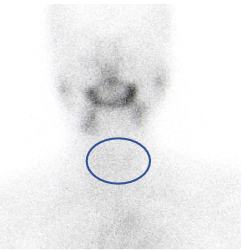

甲癌术后

d-spect怎么检查【科普先锋】甲状腺也有“冷”和“热”?核医学的SPECT检查告诉你答案_https://www.jmylbn.com_新闻资讯_第7张